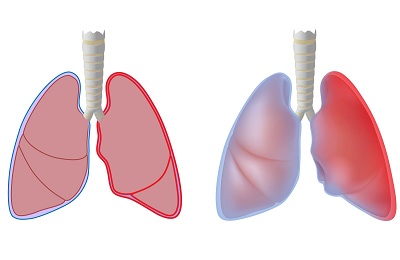

Пневмония может привести к срастанию листков плевры. Один лист выстилает грудную клетку, а другой – легкое. Если воспалительный процесс из легких перетекает в плевру, то происходит выброс фибрина, который приводит к склеиванию. Именно так и образуются спайки.

В таких случаях они бывают одиночные и множественные. В тяжелых состояниях вся плевра может быть покрыта спайками. Это приводит к ее смещению и деформации, затруднению дыхания.

В плевре спайки представляют собой соединительную ткань, растущую между оболочками легкого и грудной клетки.

Они могут иметь единичную структуру, а могут так разрастаться, что в конечном итоге занимают всю плевральную полость. В этом случае нужна экстренная медицинская помощь.